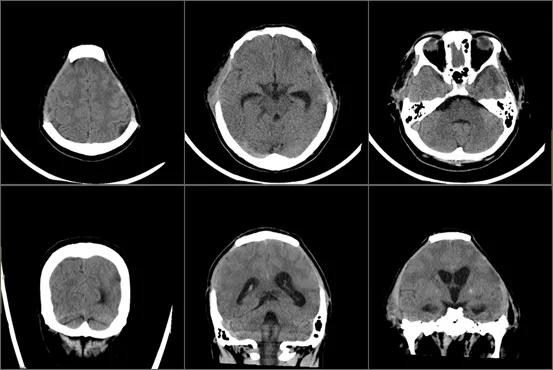

如今经过一个多月的康复治疗,梁的状态已经好了很多,可以独立完成吃饭、穿衣等精细活动,复查影像,混合积液较前吸收,颅内病灶也有了好转。